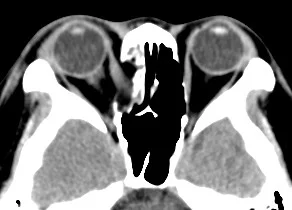

【110-2 醫學(六) 第73題】35歲病人車禍顏面骨折,合併有複視(右眼異常),接受電腦斷層檢查,下列敘述何者錯誤?